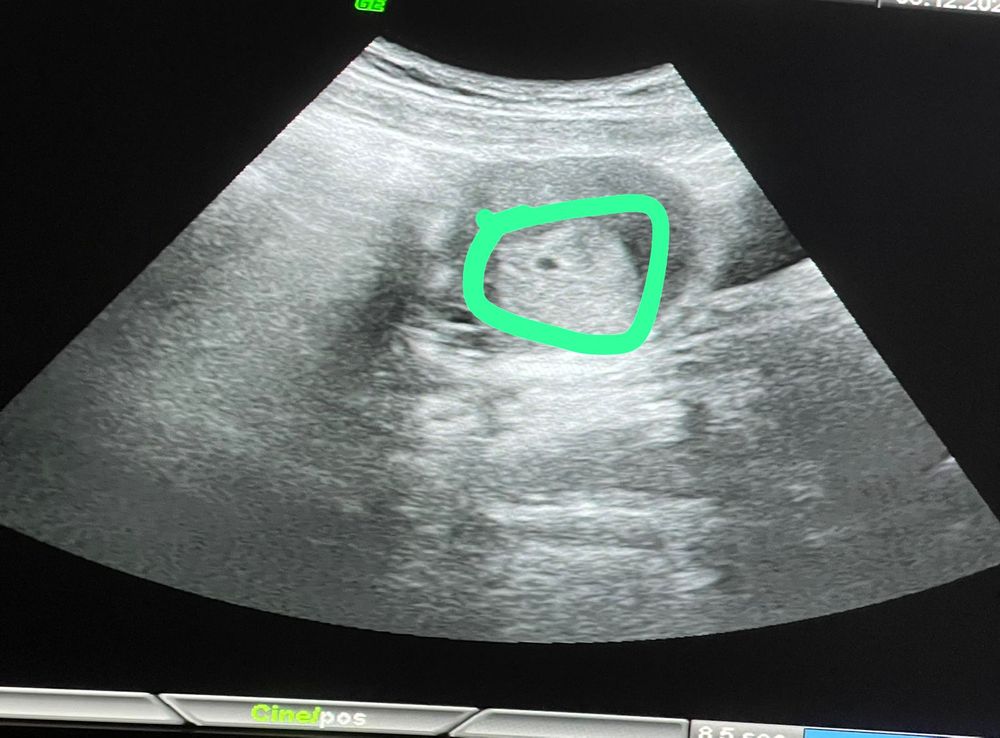

Первое узи .Хгч около 900

Беременность- 1 триместр ( только до 10 недель)

Пока видно только плодное яйцо, сказали сделать повторное через две недели.Не могу нормально порадоваться, боюсь и переживаю за все.Б первая.К кого такое было? Как справиться? Ночью все мысли об этом , естественно плохо сплю